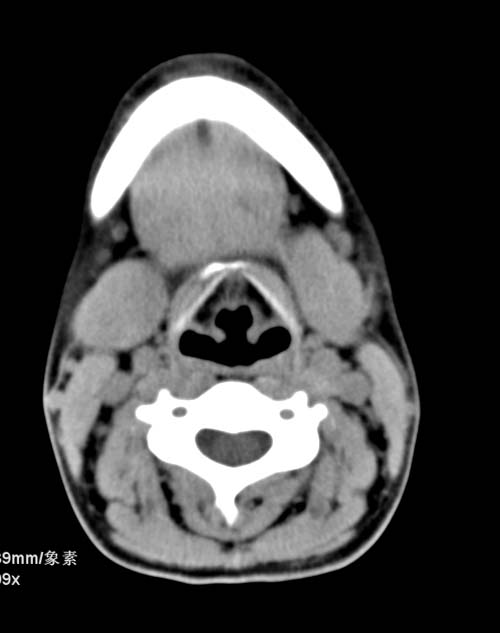

标题: CT22662:女 23 自述双侧颌下腺肿大年余 近来疼痛 左侧明显 [打印本页]

标题: CT22662:女 23 自述双侧颌下腺肿大年余 近来疼痛 左侧明显

见双侧颌下腺略肿大  未见结石及钙化 考虑双侧慢性炎症 ?请指教